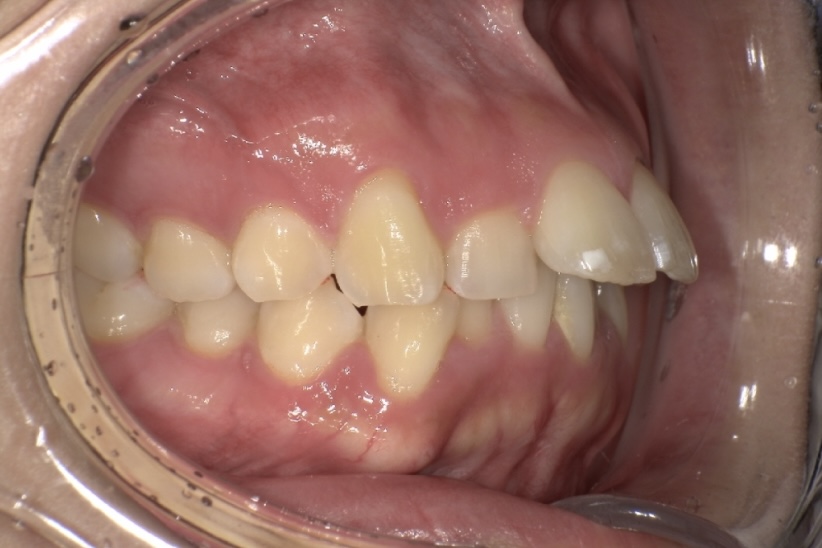

今回の症例の患者さまは30代女性で、出っ歯、下の前歯のガタつき、前歯で噛めないことを主訴にご来院されました。

診断の結果、上顎前歯の唇側傾斜が強く、歯並びの状態だけを見ると抜歯を検討するケースでしたが、患者さまの「できるだけ抜歯は避けたい」というご希望を踏まえ、奥歯の遠心移動とIPR(歯と歯の間をわずかに調整する処置)を適切に組み合わせることで、抜歯を行わずに治療を進めました。

その結果、前歯の突出感や下の前歯のガタつきが改善し、前歯でしっかり噛める機能的な咬み合わせを獲得することができ、見た目と機能の両面で良好な結果が得られた症例です。

BEFORE